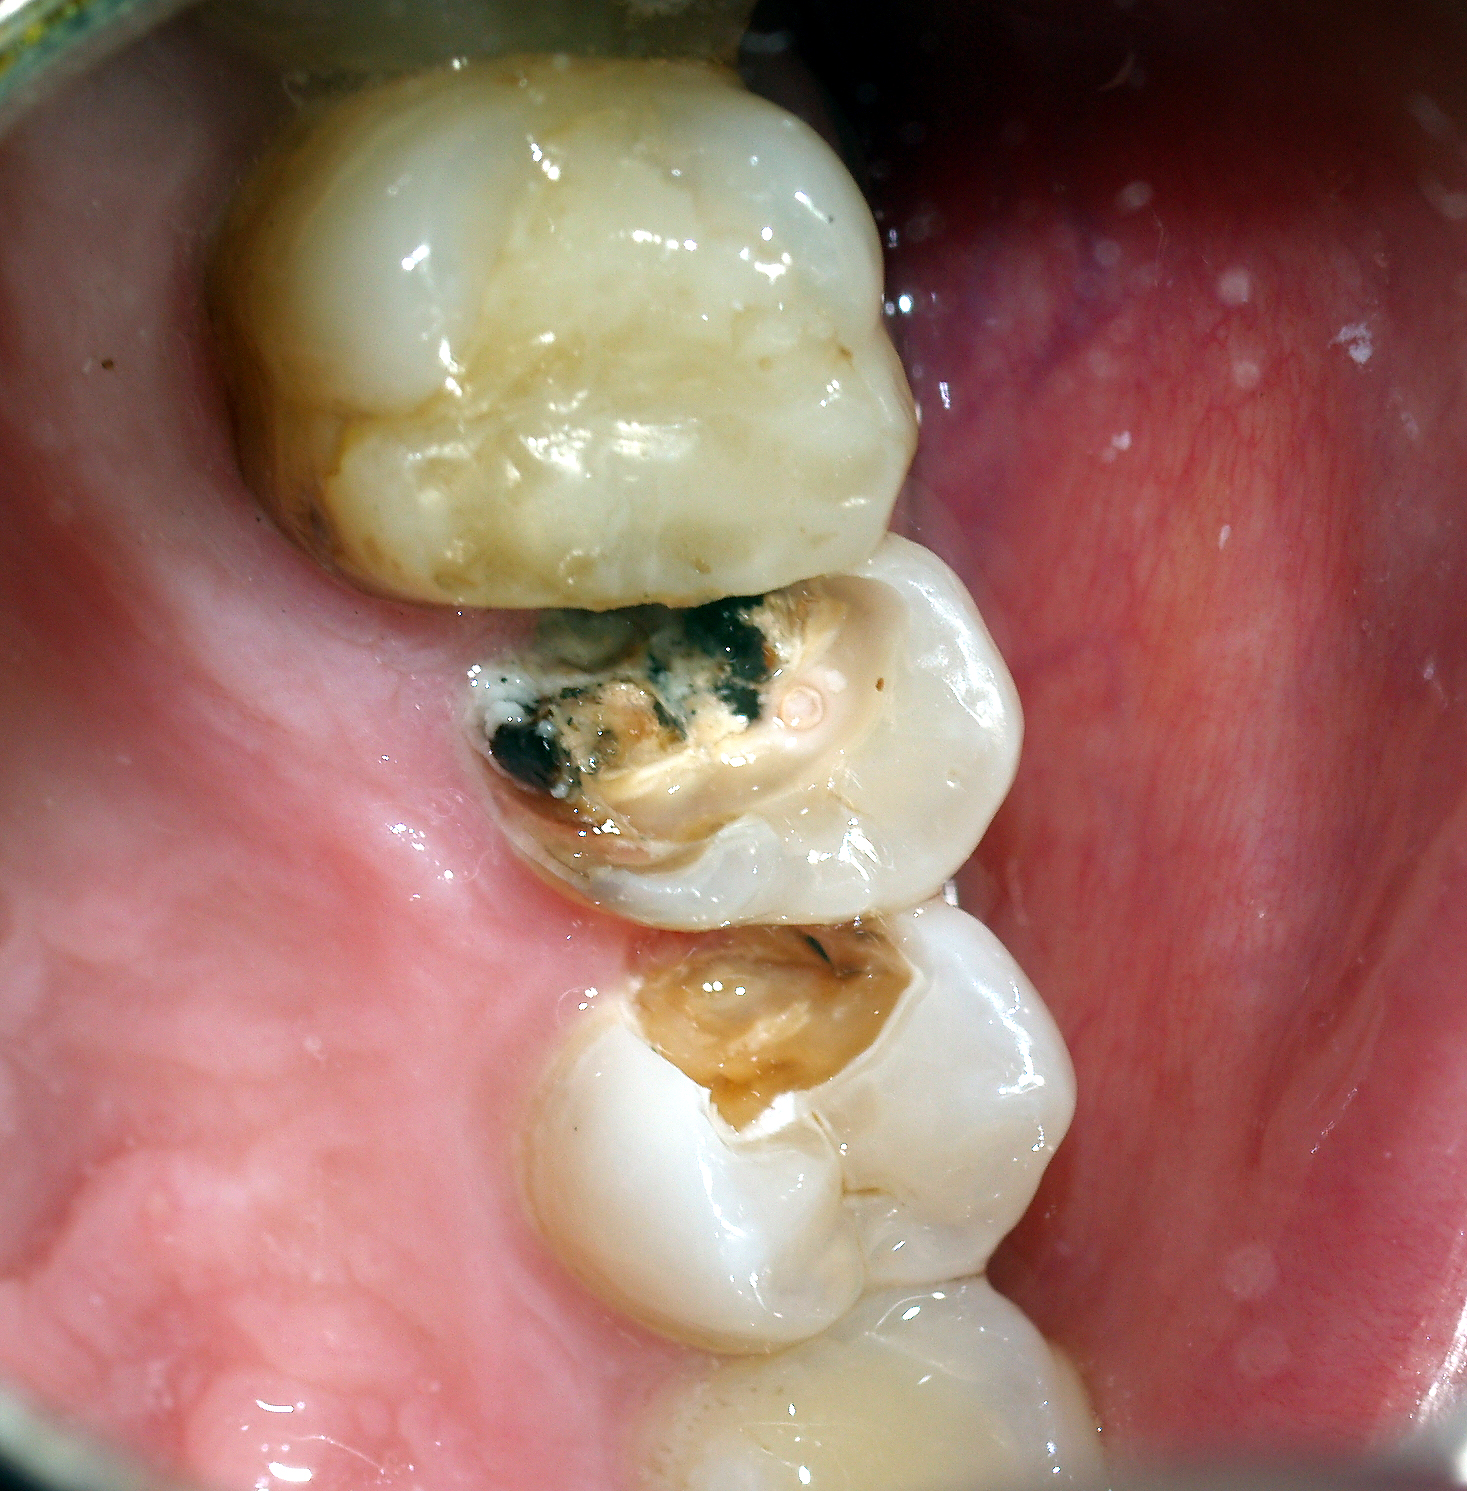

Naprawa i usuwanie wkładów koronowo-korzeniowych - galeria